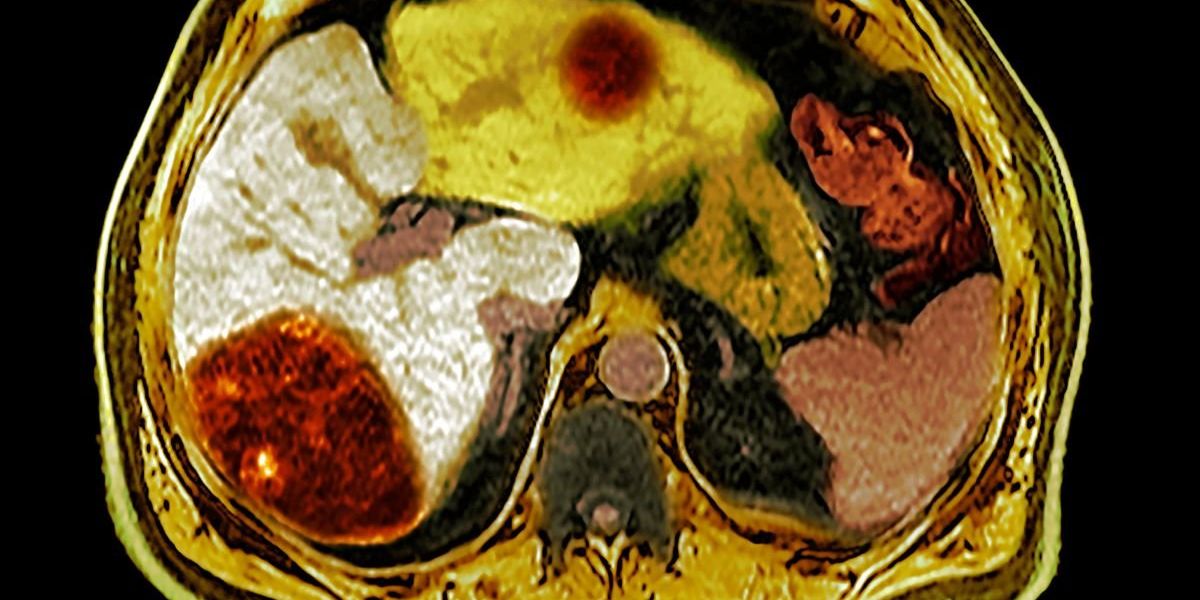

The liver is one of the body’s quiet workhorses, filtering toxins and helping to digest the food we eat. When it begins to enlarge, however, the change is often silent.

Julia Warter received a diagnosis of an enlarged liver following a series of physical symptoms that indicated her body was struggling. Her liver had swelled to 19cm before she managed to reduce it to a healthier measurement of 16cm.